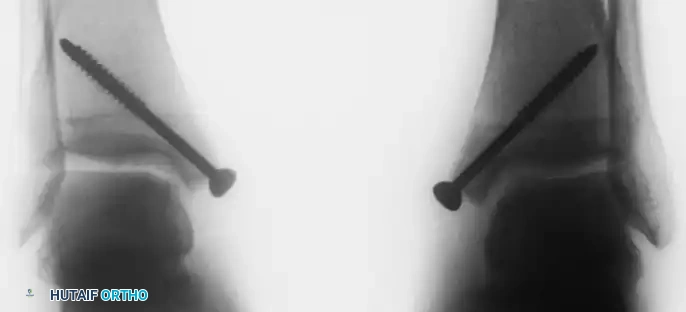

Retrograde drilling of an osteochondral lesion. After confirming intact cartilage, the subchondral lesion is drilled in a retrograde fashion and grafted.

Intraoperative fluoroscopy confirming the trajectory of the retrograde drill.

- Pre-drilling: Before the osteotomy, two parallel holes are drilled from the tip of the medial malleolus proximally into the tibial metaphysis. These are tapped for 4.0-mm cancellous screws to ensure perfect anatomic reduction during closure.

- Closure: The malleolus is reduced and secured with the previously selected screws.